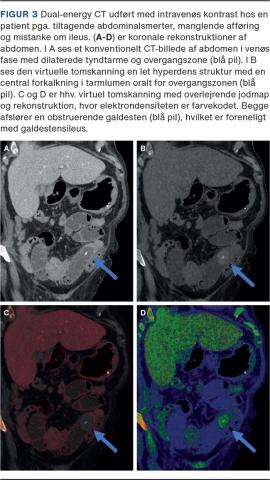

I den akutte diagnostik kan DECT bidrage i diagnosticeringen af akut tarmiskæmi ved brug af VM-rekonstruktioner og jodmaps, som kan fremhæve hypoperfunderede tarmsegmenter [16]. DECT er ligeledes pålidelig i differentieringen mellem urat- og nonuratsten i urinvejene [17], og visse CT-negative galdesten kan visualiseres med DECT (Figur 3) [18].

Billede